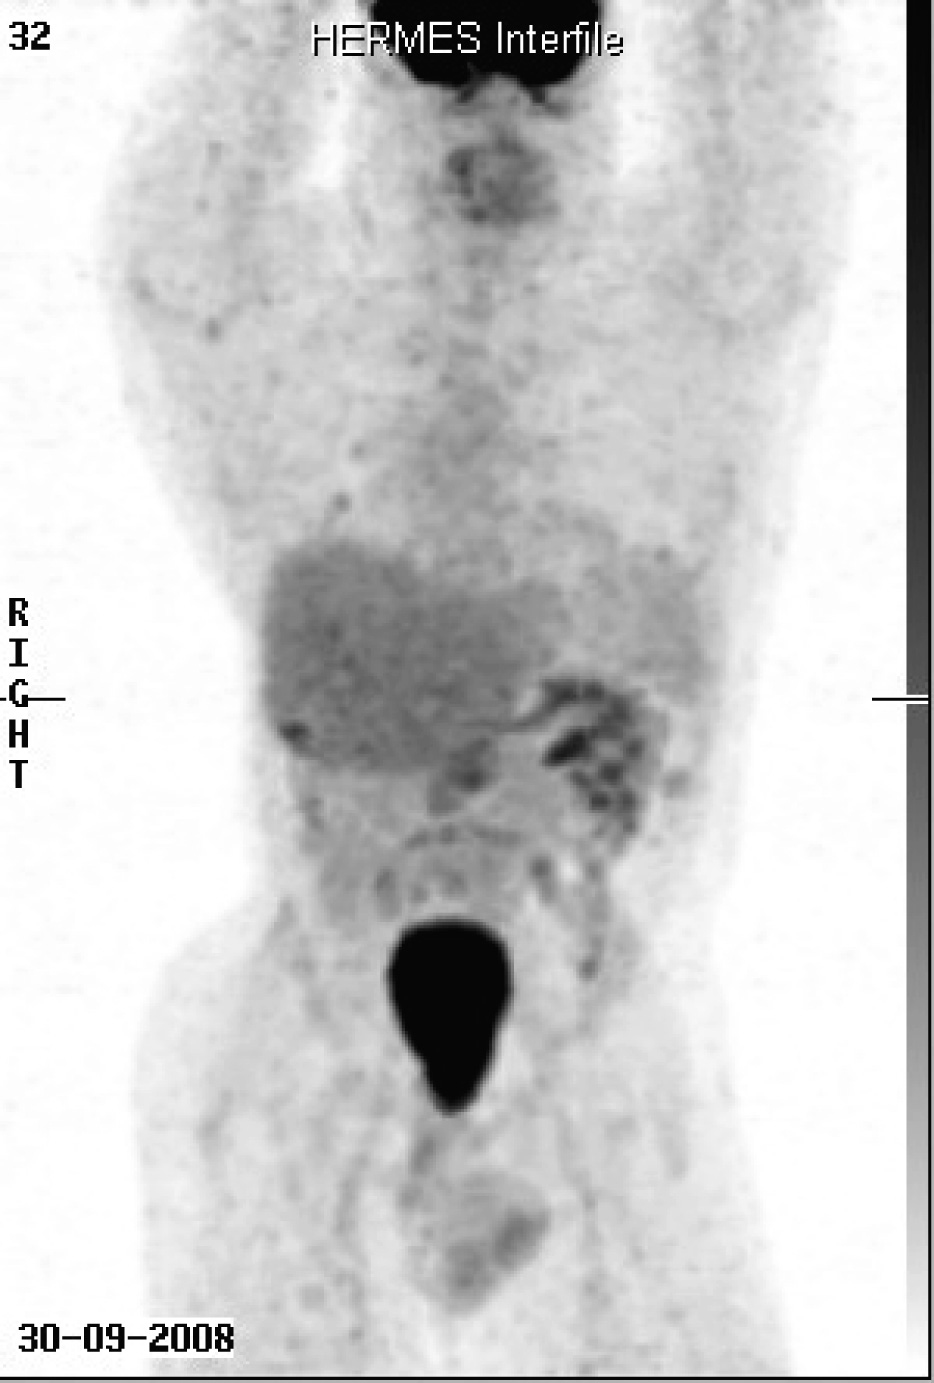

When first seen at the Cancer clinic, he appeared to be a pleasant, average built man with extensive scoliosis of his spine. He had an enlarged liver and axillary and submental lymphadenopathy. He underwent an excision biopsy of the axillary node. Histopathology was consistent with leiomyosarcoma, with well encapsulated, moderately pleomorphic and mitotically active smooth-muscle tumor. Desmin stain was positive and smooth muscle actin stain showed patchy positivity; AE1/AE3, S100 and C-Kit and EBER were all negative. Staging CT scans were performed which showed multiple metastases (Fig. 1). A staging positron emission tomography-CT scan showed uptake in the para-aortic region, the liver, a nodule inferior to the spleen, a nodule anterior to the proximal right latissimus dorsi muscle and variable uptake in the pulmonary nodules (Fig 2). The investigations confirmed a diagnosis of RIS of LMS subtype, with dominant mass in the previous radiotherapy site and extensive metastases almost three decades after his initial treatment. He was offered palliative chemotherapy, but he declined and went onto having various alternative therapies and finally succumbed to his cancer nearly 12 months after the diagnosis.

![]() Click for large image | Figure 2. Staging positron emission tomography-CT scan showed uptake in the para-aortic region, the liver, a nodule inferior to the spleen, a nodule anterior to the proximal right latissimus dorsi muscle and variable uptake in the pulmonary nodules. |